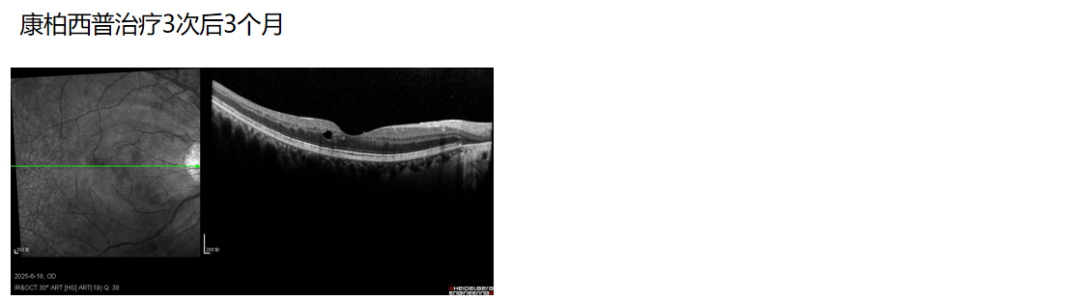

根据患者病史、症状、眼部体征及辅助检查,诊断为右眼CRVO、屈光不正。完善生化常规、凝血常规、传染病检测、自身免疫性抗体检测、ANCA抗体检测、抗磷脂抗体检测、血半胱胺酸检测、心脏彩色超声、颈动脉彩色超声检查等均未见明显异。考虑到FFA显示静脉管壁荧光着染,提示存在静脉炎症,给予右眼康柏西普玻璃体腔注射治疗(3+PRN方案),联合全身口服小剂量糖皮质激素辅助抗炎治疗。康柏西普治疗1次后,右眼视力即提升至1.0,ME消退,CRT从治疗前的549 μm降低至228 μm。连续3次治疗后25 d,视力维持在1.0,ME无复发,CRT 227 μm,连续3次治疗后3个月,仅黄斑区颞侧外核层见小囊泡改变,补充注射1针后1周,囊泡消失,视力维持在1.0。

图:右眼进行康柏西普治疗前后的OCT